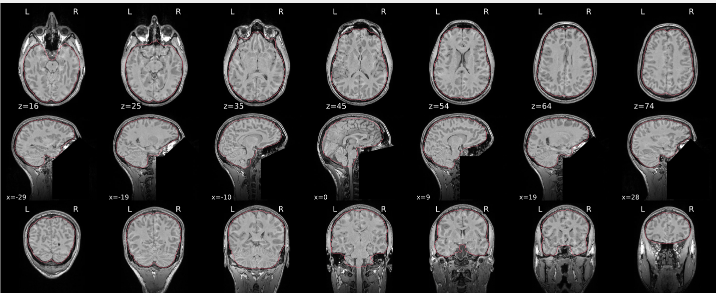

T1w skull stripping

Skull stripping is the process separating the brain (cortex and cerebellum) from the skull. The red line follows the outline of the brain and it separates it from the skull.

Example of a good subject

- There are no skull stripping errors, such as portions of the brain missing, or too much of the skull retained

- The red line follows the outline of the brain

Example of a bad subject

- There are skull stripping errors, such as portions of the brain missing, or too much of the skull retained

- NOTE: check all the images (slices) in the report. If only one image (slice) looks problematic, it is possible that the subject is okay and it is just a visual issue in that particular screenshot

Summary

| Good | Bad |

|---|---|

| The brain is fully inside the red line | Structures like the cranium or the eyes are inside the red line |

| No important brain structures are outside of the red line red line follows the natural outline of the brain | Important brain structures are missing inside of the red line |

-> if only one slice is problematic, it could be an issue related to the visual depiction of the data instead of an issue related to the test subject